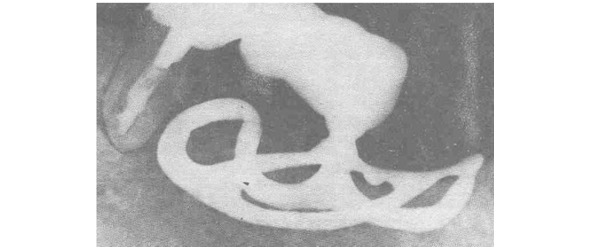

Игольчатый имплантат предложили Д-р Шершеве (Chercheve) и д-р Скайлом (Scialom) 1940—1980 гг

Конечно при разработки данного вида опоры не было соблюдения понятий биофизики и биомеханики поведения имплантата в костной ткани. Да и сама биомеханика, как наука только закладывалась.

Игольчатый имплантат смог обеспечить неподвижную опору в полости рта. И как этап эволюции его заслуга не подлежит сомнению.

Такие опоры не долговечны, но достаточно легко заменимы. Надежность ортопедической конструкции обеспечивается значительным количеством опор.

Следующим шагом в эволюции можно считать спиралевидные имплантаты. Грубо говоря игольчатому имплантату придали форму спирали для увеличения площади соприкосновения с костной тканью. Такое увеличение площади привело к большей стабильности имплантатов в костной ткани.

Д-р Шершеве (Chercheve) и д-р Скайлом (Scialom) 1940—1980 гг, а так же д-р Формиджини (Formiggini) начали применять спиральные имплантаты

Спиралевидный имплантат – начало эры современной дентальной имплантации.